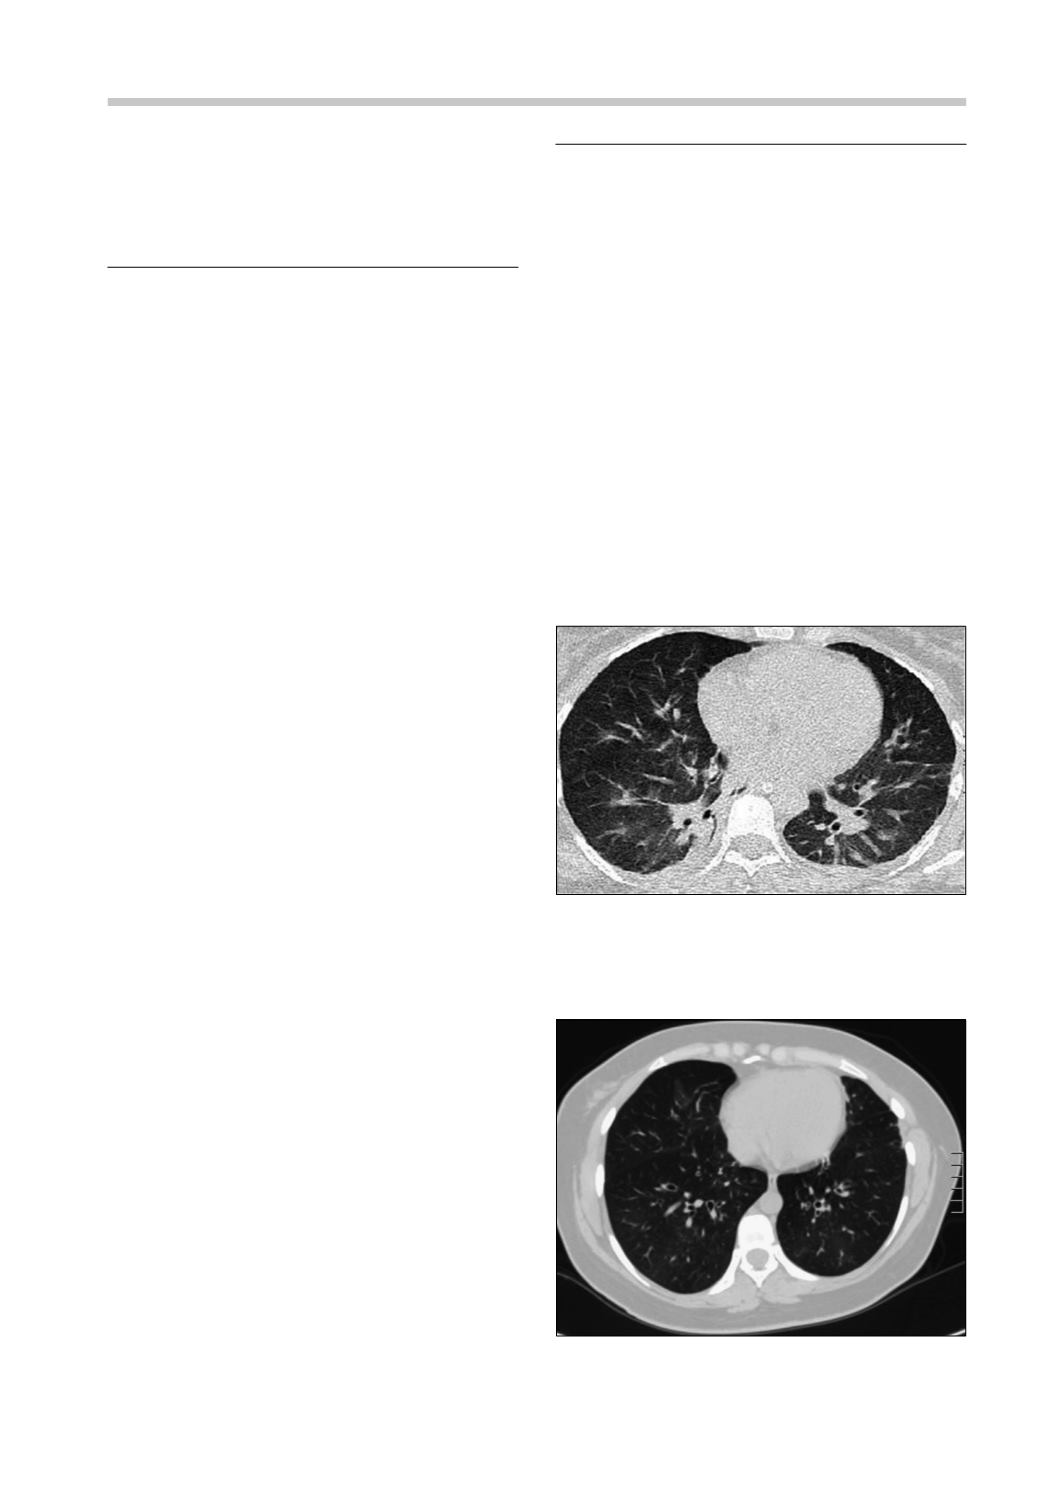

La tomografía axial computada (TAC) de tórax

de ingreso muestra opacidades tenues peribron-

covasculares, vidrio esmerilado de distribución

parcheada, difuso y bilateral (Figura 1), cuadro

clínico-radiológico consistente con una injuria

pulmonar aguda.

La TAC de tórax muestra una bronquiolitis

difusa asociada a patrón en mosaico y bronquiec-

tasias cilíndricas (Figura 2).

Figura 1.

TAC de tórax al ingreso. Compromiso intersti-

cial difuso con opacidades en parches, áreas de consolida-

ción en lóbulos inferiores y zonas de atrapamiento aéreo.

Figura 2.

TAC de tórax a los 2 años del accidente

inhalatorio. Zonas de atrapamiento aéreo marcado y

engrosamiento de paredes bronquiales especialmente a

nivel central.